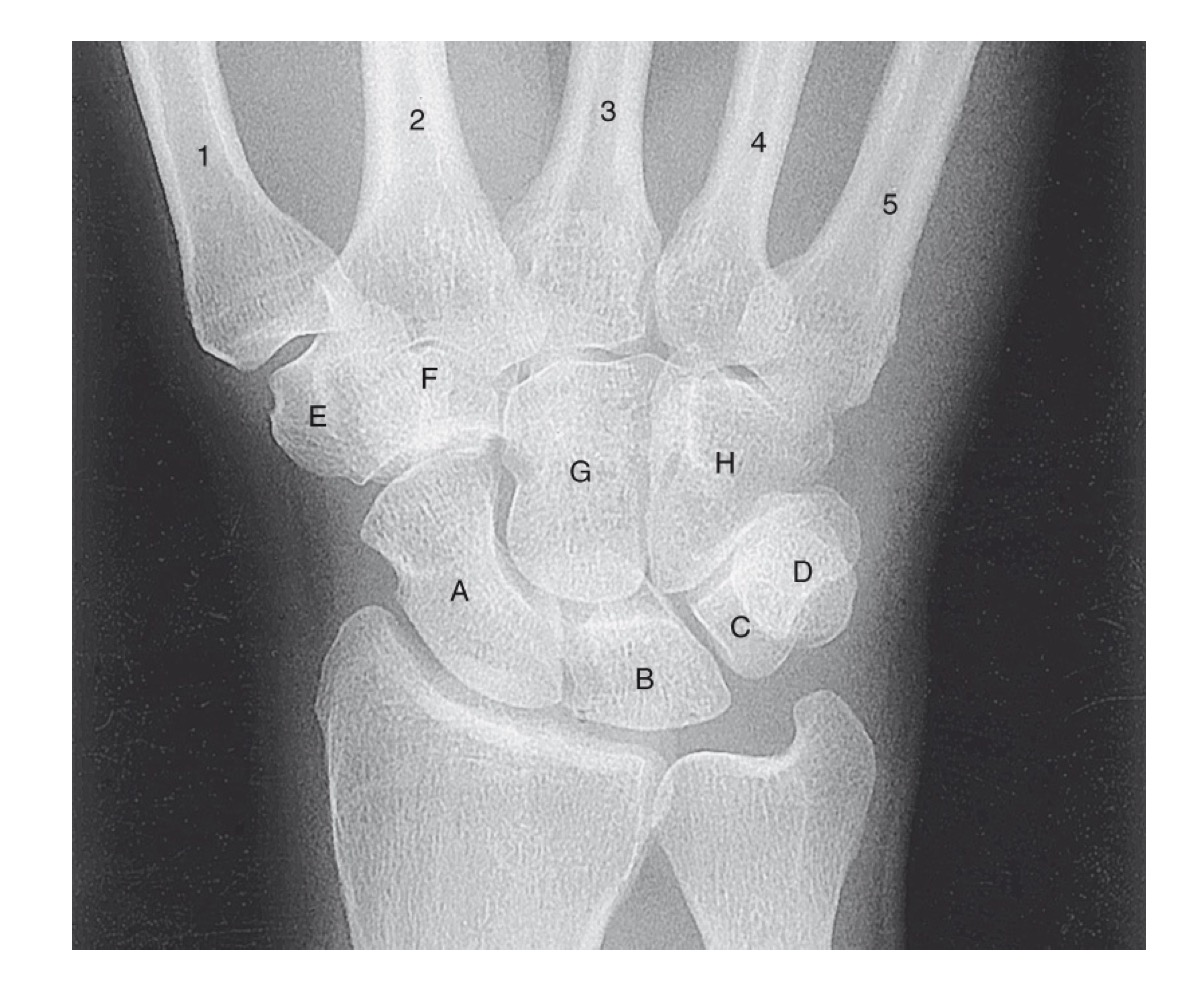

<p>what is A</p>

what is A

scaphoid

<p>what is B</p>

what is B

lunate

<p>what is C</p>

what is C

triquetrom

<p>what is D</p>

what is D

pisiform

<p>what is E</p>

what is E

trapezium

<p>what is F</p>

what is F

trapezoid

<p>what is G</p>

what is G

capitate

<p>what is H</p>

what is H

hamate